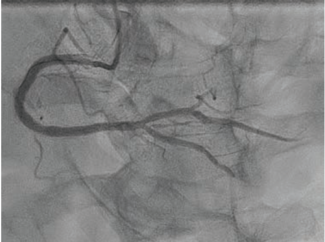

The authors share a case of a large LAD-to-right-sided coronary cameral fistula that produced angiographic coronary steal but no significant shunt, allowing for successful conservative management.